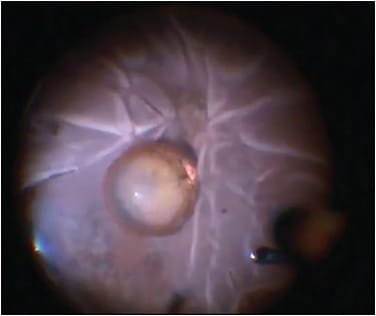

Once the anterior chamber is free of prolapsed vitreous, any smaller nuclear or epinuclear fragments still available anterior to the posterior lens capsule may be carefully removed (Figure 1). Dispersive viscoelastic can be used to bring fragments into the iris plane. This viscoelastic can be injected through a limbal incision or through the pars plana (posterior assisted levitation [PAL]).7 In general, the cataract surgeon may wish to avoid mechanical PAL with a spatula or other device, as such maneuvers may inadvertently cause further retinal traction.

Once the lens fragments are at or above the iris plane, the surgeon can consider employing a Sheet’s glide or intraocular lens (IOL) scaffold technique8 to prevent further posterior lens displacement or vitreous prolapse while the fragments are aspirated. Manual extraction may be preferred for larger lens fragments for situations in which phacoemulsification may worsen posterior displacement and cause increased vitreoretinal traction.